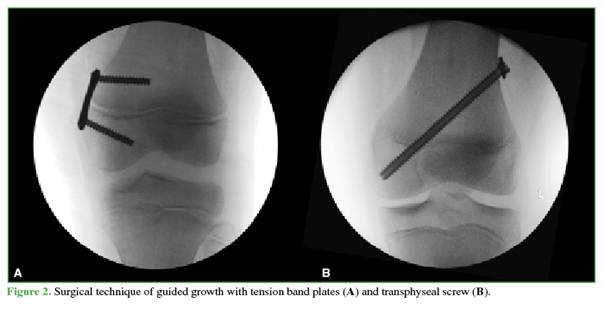

After the arthroscopic procedure, guided growth is performed. If the estimated remaining growth exceeds two years, tension band plates are used;8 if less growth remains, transphyseal screws are employed (Figure 2).9

Skeletal maturity is calculated with the FELS method.10 Tension band plates are placed under fluoroscopic guidance. A 1.6 mm guide pin is inserted into the epiphyseal region of the distal femur, approximately 6–8 mm distal to the physis (the distance between the proximal and distal holes of a 12 or 16 mm plate). The plate is then advanced along the guidewire into the subcutaneous tissue to allow placement of the second guide pin proximally into the metaphysis in a divergent orientation. Proper positioning is verified fluoroscopically. The trial plate is removed, and a skin incision (typically 2–3 mm) is made between the two guide pins, extending as needed. The plate is then dissected down to the periosteum, positioned in place, and 4.5 mm cannulated screws are inserted over both guide pins using standard technique. For transphyseal screws, a guide pin is placed obliquely from distal to proximal under fluoroscopic control.

After confirming position, the tract is reamed from proximal to distal, and a 7.0 mm fully threaded cannulated screw is inserted percutaneously. Screw length is selected to ensure at least three threads engage the epiphysis. A washer is used to facilitate future removal. Finally, all incisions are closed in layers, and a sterile dressing is applied to the surgical wounds.

This article provides information on the surgical technique used by the authors for discoid meniscus preservation surgery in combination with guided growth in patients with open physes. The surgical technique described involves saucerization of the external discoid meniscus, its repair in the presence of injury or peripheral instability, as well as the incorporation of guided growth during the same surgical procedure, using either tension band plates or transphyseal screws.

Historically, angular limb deformities have been corrected by osteotomy. Although effective, osteotomy is an invasive procedure requiring prolonged recovery and carrying risks of complications such as infection, delayed bone healing, and the need for postoperative immobilization.17 In recent decades, the development of guided growth techniques has revolutionized the management of these deformities in patients with open physes. Techniques such as the use of extraphyseal tension band plates18 or transphyseal screws9 allow the natural growth of the limb to be modulated, gradually guiding it into correct alignment. Unlike osteotomy, guided growth is minimally invasive, reducing recovery time, postoperative discomfort, and the risk of complications. Consequently, guided growth has become the treatment of choice for angular deformities in the pediatric population, minimizing the need for invasive interventions and offering a safe and effective alternative.4